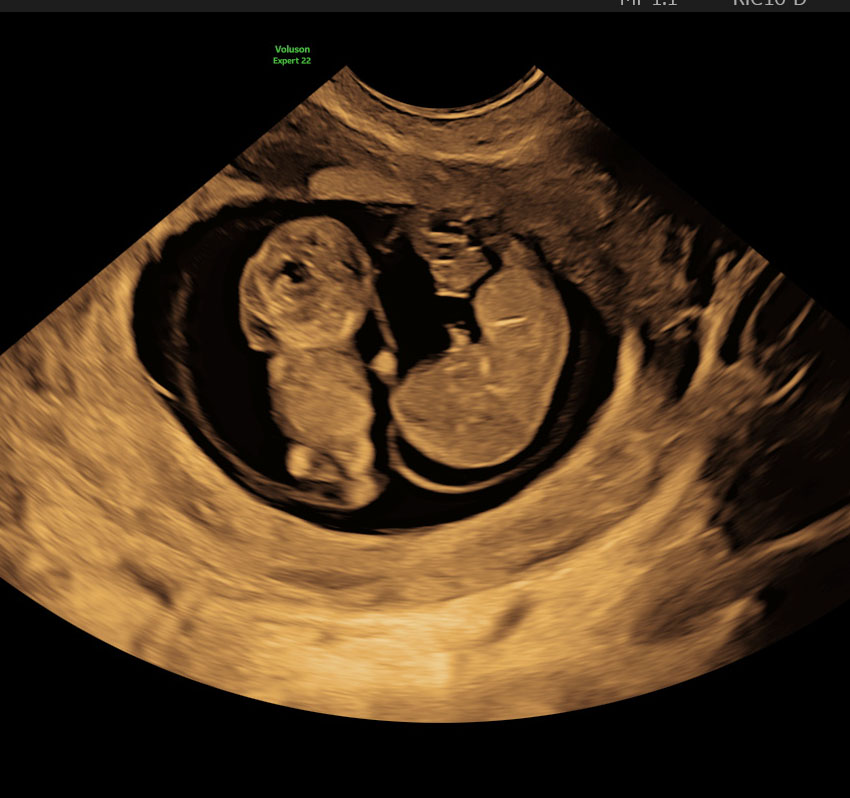

- Lemmer: Arme og ben er nu mere udformede, og du kan se små albuer og knæ. De små hænder og fødder er begyndt at danne sig tydeligere, og selvom bevægelserne stadig er små, er der begyndende aktivitet, som en ultralydsscanning kan afsløre.

- Indre Organer: De indre organer, såsom hjertet, leveren og nyrerne, er nu godt udviklede. Hjertet slår kraftigt, og denne aktivitet kan ses på en ultralydsscanning, som kan være en betryggende bekræftelse på, at alt udvikler sig som det skal. Lungernes udvikling fortsætter, og de første blodlegemer dannes i leveren.

- Bevægelse: Selvom du ikke kan mærke bevægelserne endnu, kan tidlige ultralydsscanninger vise, hvordan embryoet bevæger sig. Det kan være en spændende oplevelse at se de små bevægelser, som endnu ikke er mærkbare for dig.